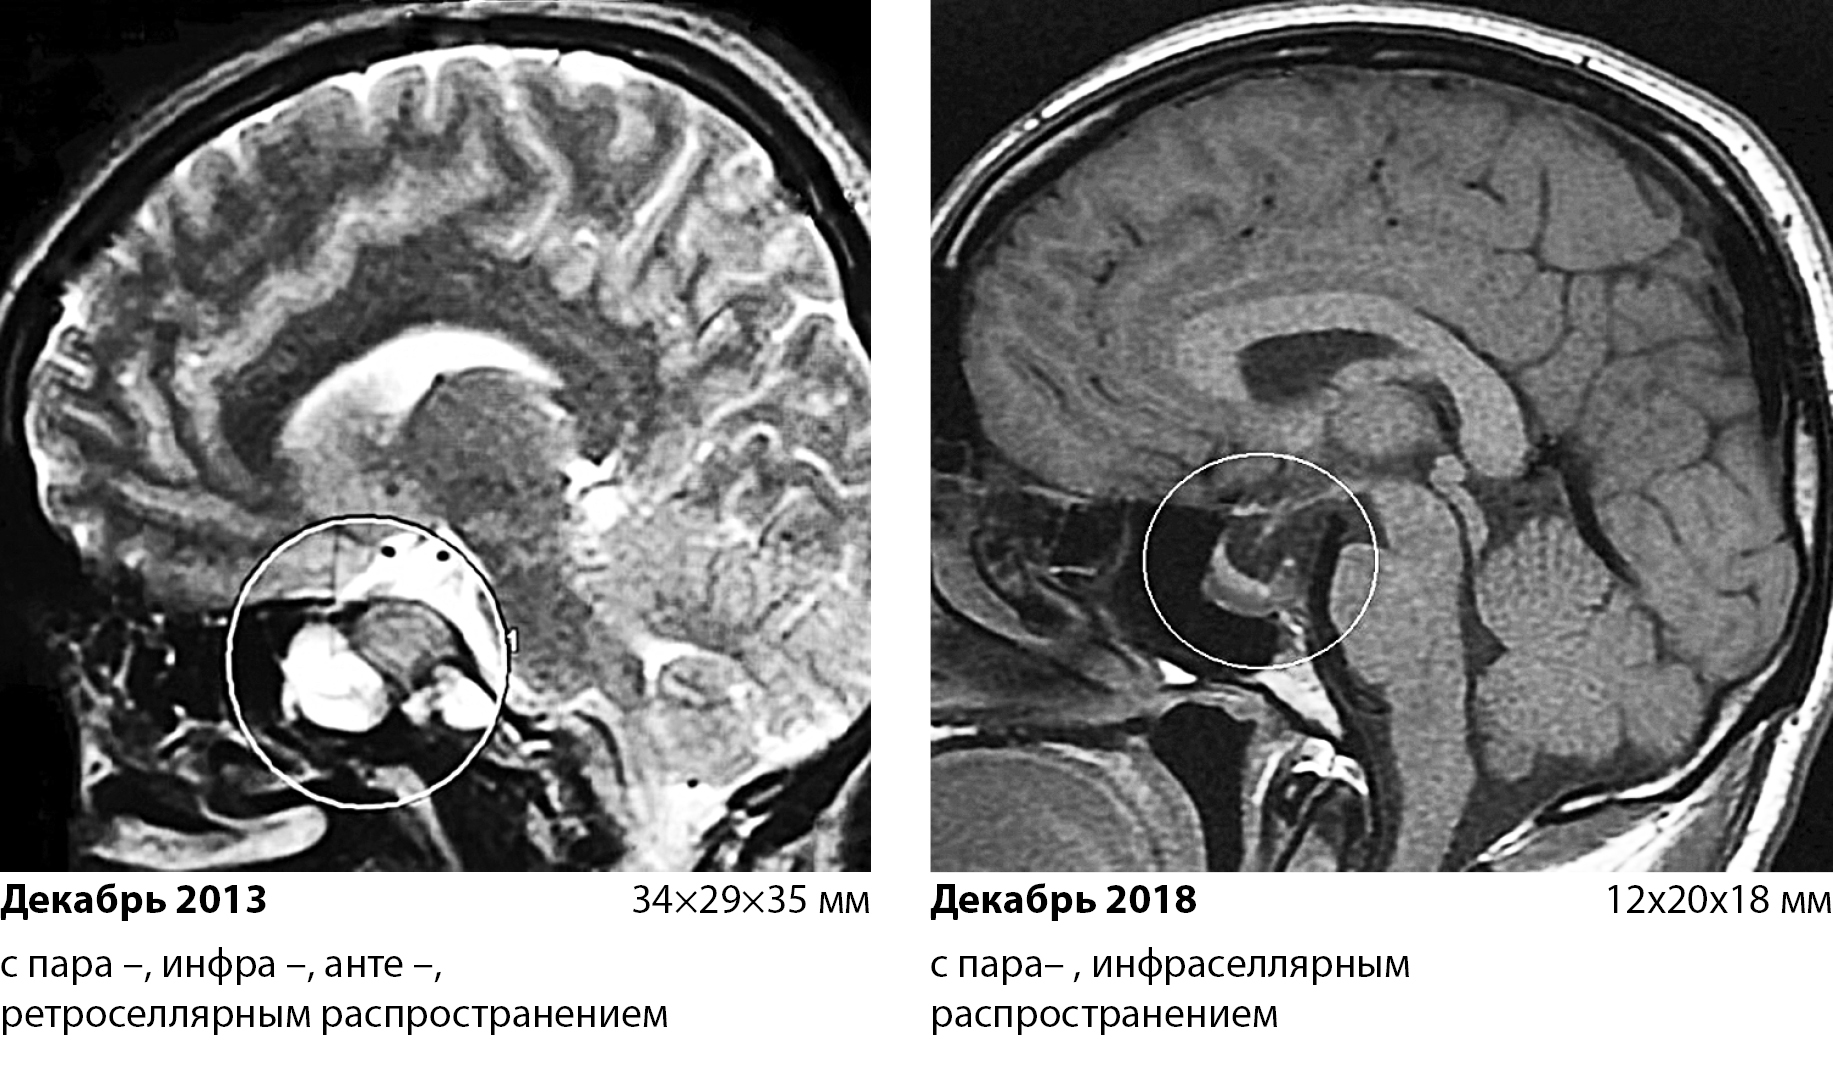

2. Fig. 2. Change in the size and distribution of the formation of the pituitary gland after 5 years of therapy with cabergoline | |

3. Рис. 2. Изменение размеров и распространения образования гипофиза через 5 лет терапии каберголином.(декабрь18)(декабрь13) | |